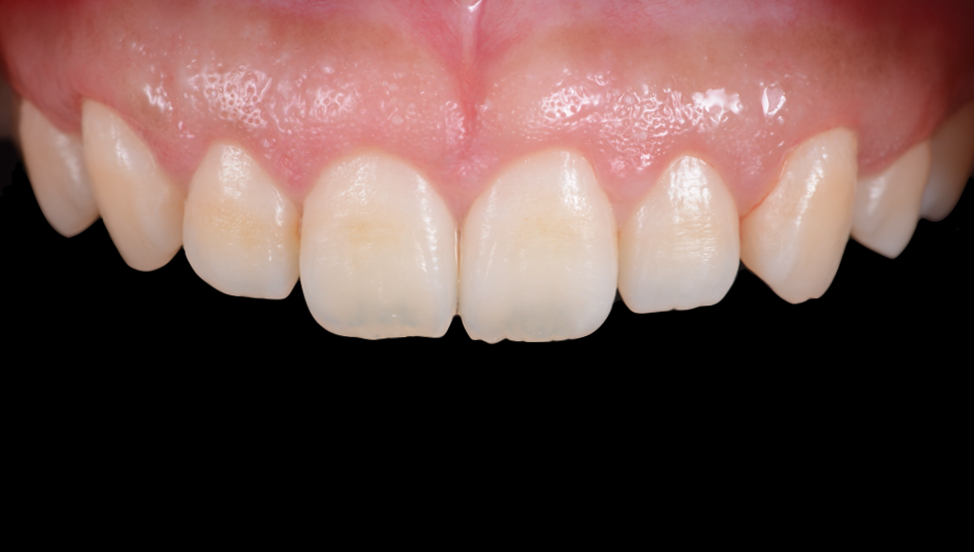

FGG(遊離歯肉移植術)で歯肉増大と歯の根元を被覆した症例